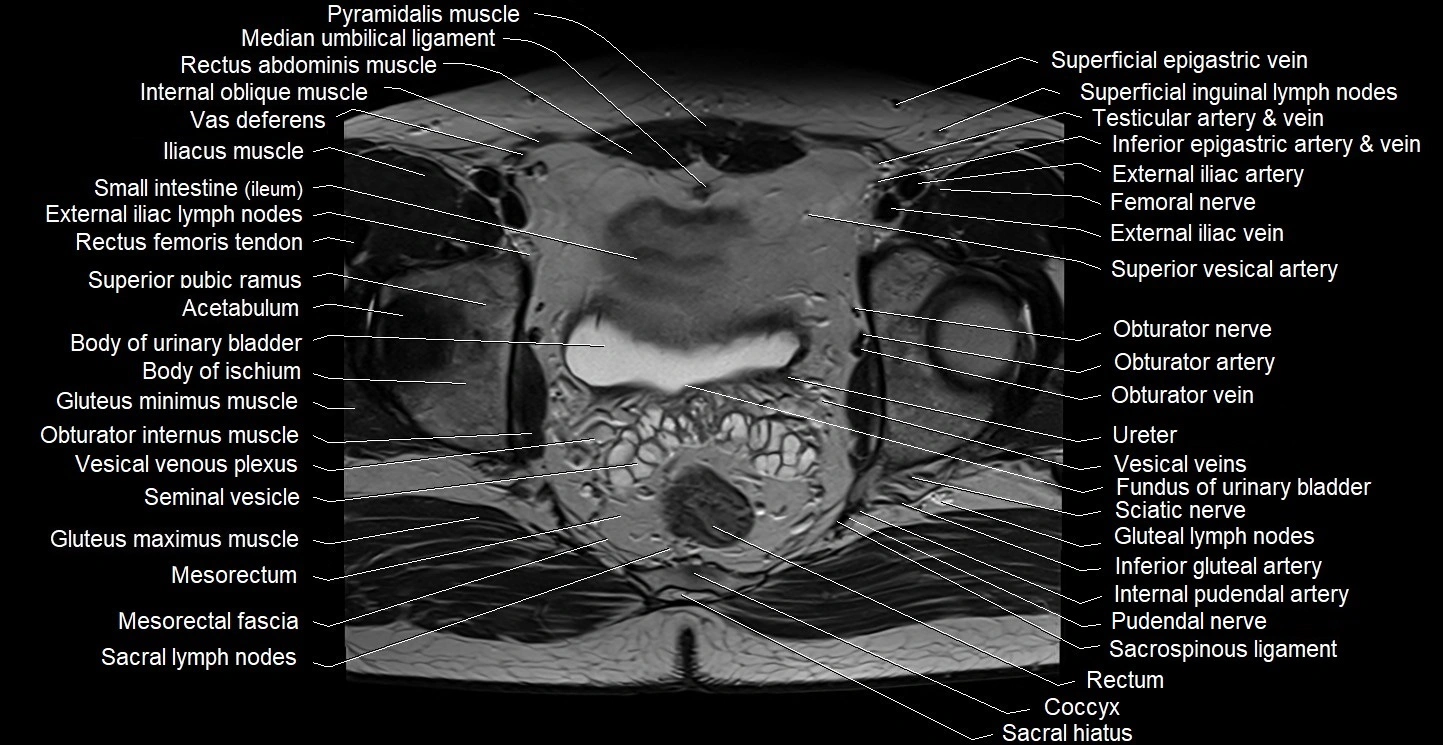

- Body of urinary bladder

- Fundus of urinary bladder

- Gluteal lymph nodes

- Internal oblique muscle

- Mesorectal fascia

- Mesorectum

- Obturator internus muscle

- Piriformis muscle

- Pudendal nerve

- Sacral lymph nodes

- Sacral plexus

- Sacrospinous ligament

- Sciatic nerve

- Seminal vesicle

- Superficial inguinal lymph nodes

- Trigone of urinary bladder

- Vesical veins

- Vesical venous plexus